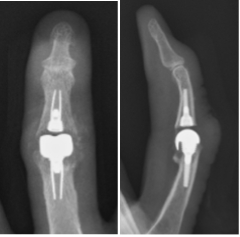

人工関節置換術

関節リウマチや変形性関節症の患者さんで、関節が破壊され機能が失われた症例に対し各関節(指、肘、肩)の人工関節置換術を行ない、関節機能の再建を行っています。

術前

右中指が屈曲変形し骨が癒合しています

術後

人工関節に置換し指が伸びました